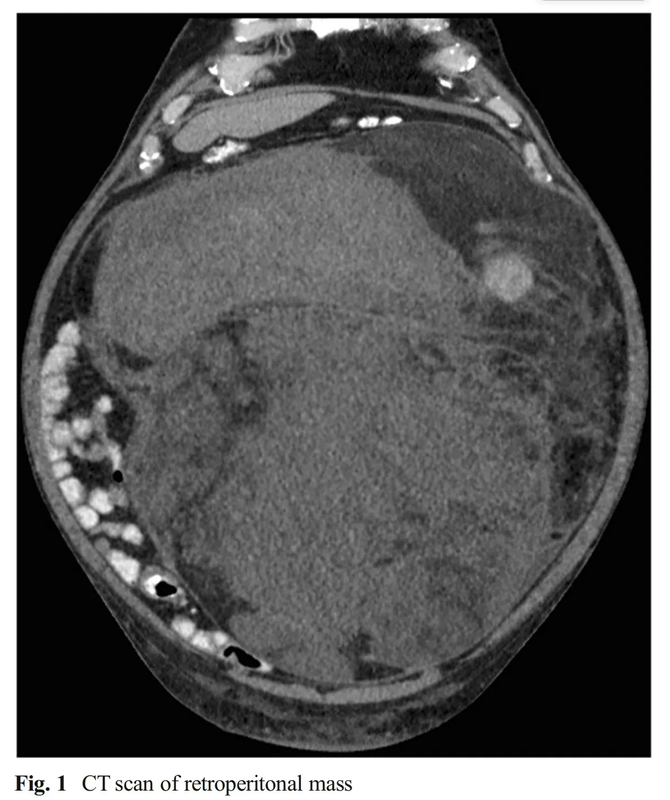

巨大腹膜后肉瘤1例

患者64歲,因腹脹就診。查體觸及一個(gè)大腫物,CT掃描提示巨大腫瘤,占據(jù)整個(gè)腹腔,導(dǎo)致臟器移位。腫瘤表現(xiàn)為后腹膜肉瘤,沒(méi)有進(jìn)行活檢。完整切除了這個(gè)40cn90磅的腫物,同時(shí)進(jìn)行了左側(cè)腎臟廣泛切除和左側(cè)結(jié)腸切除手術(shù)。手術(shù)病理符合R0切除的III級(jí)后腹膜脂肪肉瘤?;颊咝g(shù)后恢復(fù)順利,無(wú)并發(fā)癥出院。腹膜后肉瘤是少見(jiàn)腫瘤,年發(fā)病率為千萬(wàn)分之三。手術(shù)完整切除腫瘤是治療的關(guān)鍵,5年生存率可以達(dá)到50-70%?;熀头暖?,對(duì)于部分患者有效,特別是交界性,或無(wú)法切除的腹膜后肉瘤。沒(méi)有證據(jù)證明大體腫瘤完整切除后,再進(jìn)行術(shù)后放療有價(jià)值。

劉東光醫(yī)生的科普號(hào)2024年04月26日173